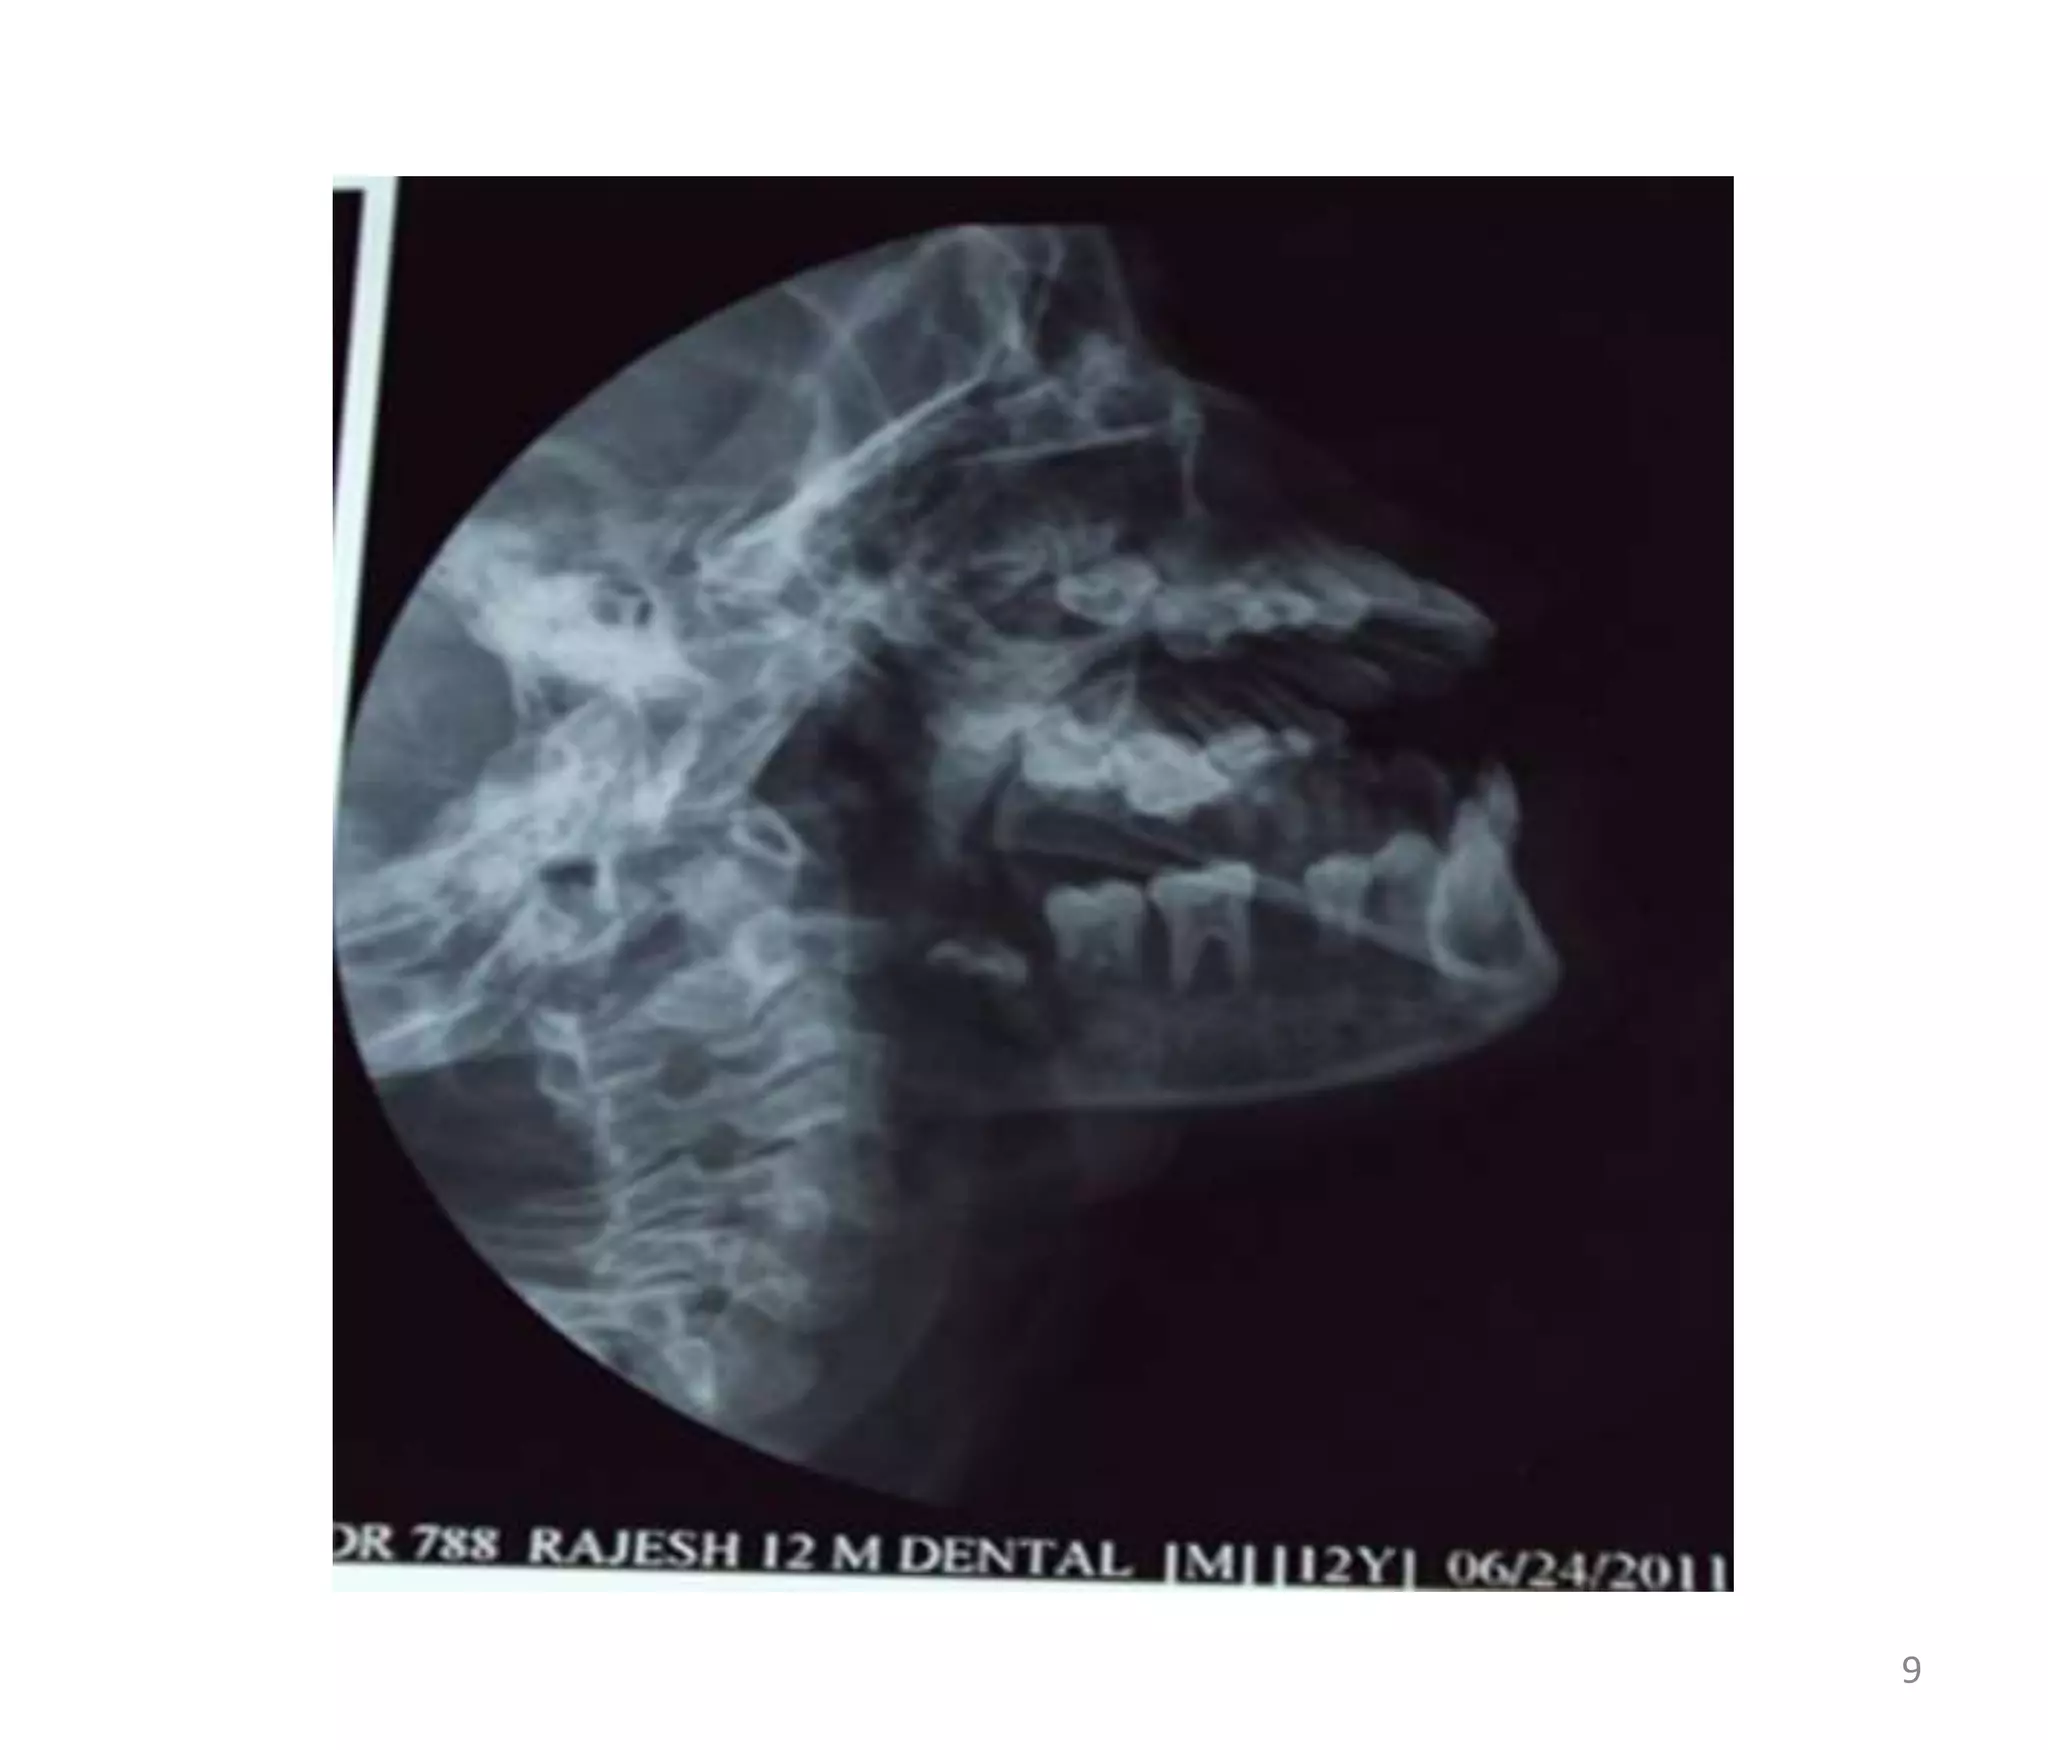

X-RAY MANDIBLE LT-OBLIQUE VIEW

 E/O ill-defined lytic lesion showing permeative

pattern of destruction involving horizontal ramus &

angle of mandible.

 Lamina dura &alveolar margin shows evidence of

destruction resulting in exfoliation of teeth.

 Impacted 3rd molar seen.

 Evidence of ill-defined soft tissue adjacent to mass

seen.

X-RAY MANDIBLE LT-OBLIQUEVIEW  E/O ill-defined lytic lesion showing permeative pattern of destruction involving horizontal ramus & angle of mandible.  Lamina dura &alveolar margin shows evidence of destruction resulting in exfoliation of teeth.  Impacted 3rd molar seen.  Evidence of ill-defined soft tissue adjacent to mass seen. 10